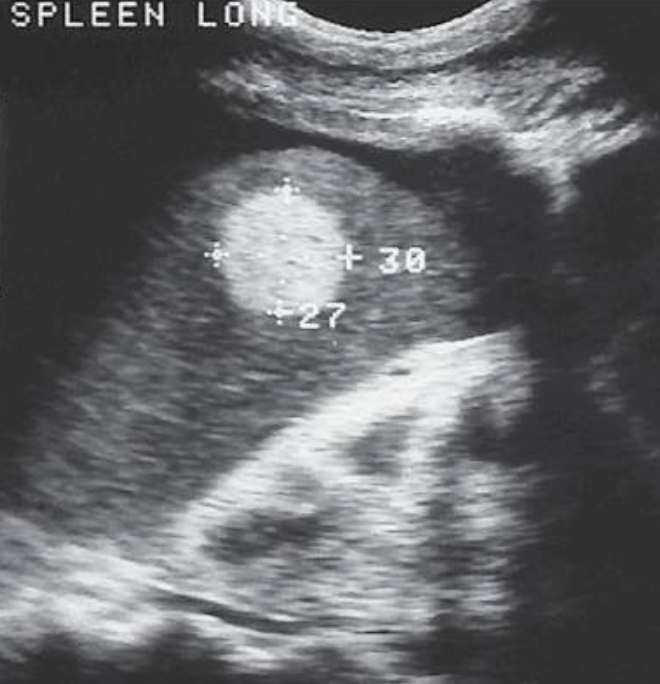

Simple Splenic Cysts → secondary cysts from trauma, infection, or infarction (technically pseudocysts, since congenital cysts are rare)

clinical hx: trauma

s/sx: asymptomatic, can have LUQ pain

2D US: round, smooth, well-defined borders, anechoic fluid-filled lumen, no internal echoes (unless complicated, can produce posterior enhancement)

color doppler: avascular

DDX: splenic abscess/infected/complicated cyst